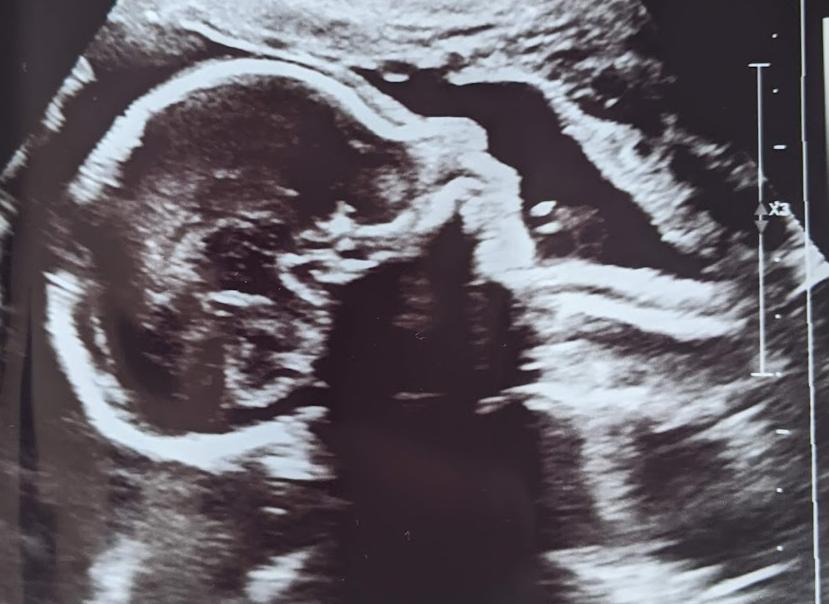

Things seem to be going well. We made it through the anatomy scan at 21 weeks, with a follow up at 24 weeks because they couldn't quite get all the images they needed. My belly is big and I look so pregnant. My sister in law is planning a baby shower. It's wild!